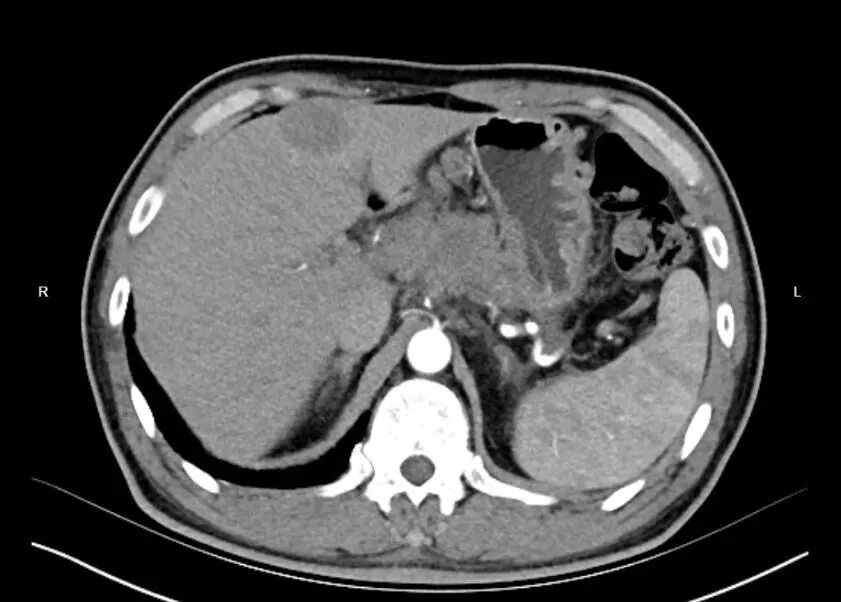

患者男性,年龄,发现肝占位一月余,于2026-03-31在超声引导下行肝占位穿刺活检。

(超声引导下可见红色区域为肝内占位灶,黄色区域为伴行动脉)(超声引导下可见红色区域为肝内占位灶,黄色区域为伴行动脉)

术后病理提示:胰腺神经内分泌癌肝转移。该技术极大减少了危险部位及出血高危患者的出血风险,尤其适用于肝、肺、肾等血供丰富组织的穿刺活检。同时减少了穿刺次数,降低患者穿刺痛苦。